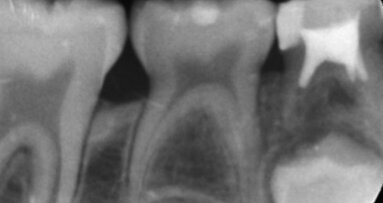

A livello occlusale problematiche di tipo parodontale e conservativo, agenesia degli incisivi laterali con persistenza del canino deciduo a dx e dell’incisivo laterale deciduo a sn, pregressa estrazione dei primi molari inferiori, presenza di residui radicolari nella zona del I primo molare superiore di dx, deviazione di entrambe le linee mediane (Figg. 5a-5c). L’analisi cefalometrica in proiezione laterale non fornisce ulteriori indicazioni (Figg. 6a-6c). La paziente chiede una riabilitazione globale, dettata soprattutto da motivi di tipo estetico. Desidera inoltre ripristinare l’integrità della dentatura in corrispondenza degli elementi decidui ancora in arcata e che stanno per esfoliare, e ripristinare la masticazione nelle zone edentule.

Al termine di questa fase è iniziata la cura ortodontica con i seguenti obiettivi: movimento radicolare di 47, movimento coronale di 37 e riapertura dello spazio, riduzione dello spazio tra 15 e 17 e successivo restauro con implantoprotesi, ripristino dello spazio per il 22, estrusione di 13 per migliorare la posizione dell’arco gengivale e successiva ricostruzione, rimodellamento interprossimale 13-11-21 per ripristinare un corretto rapporto dento-dentale (Figg. 7a, 7b).